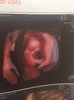

A tak poza tym tematem to wczoraj byliśmy na badaniach prenatalnych. Wszystko jest Ok :)

Madagos ale rewelacyjna fotka [emoji7] Pięknie widać maluszka! Super że wszystko dobrze [emoji8]

A tak poza tym tematem to wczoraj byliśmy na badaniach prenatalnych. Wszystko jest Ok :) Zobacz załącznik 899950

Madagos, śliczna dzidzia [emoji8]

Nie chcemy znac płci bobasa. Chcemy Kinder niespodziankę [emoji14]